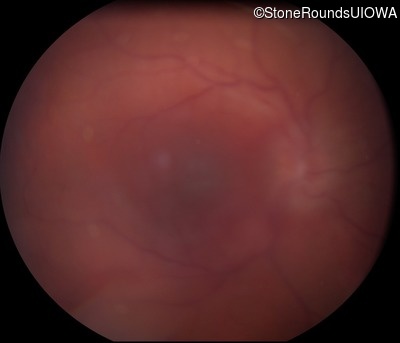

Visit at age: 33 years

Fundus Photography - Right - 20/300 sc

Exemplar